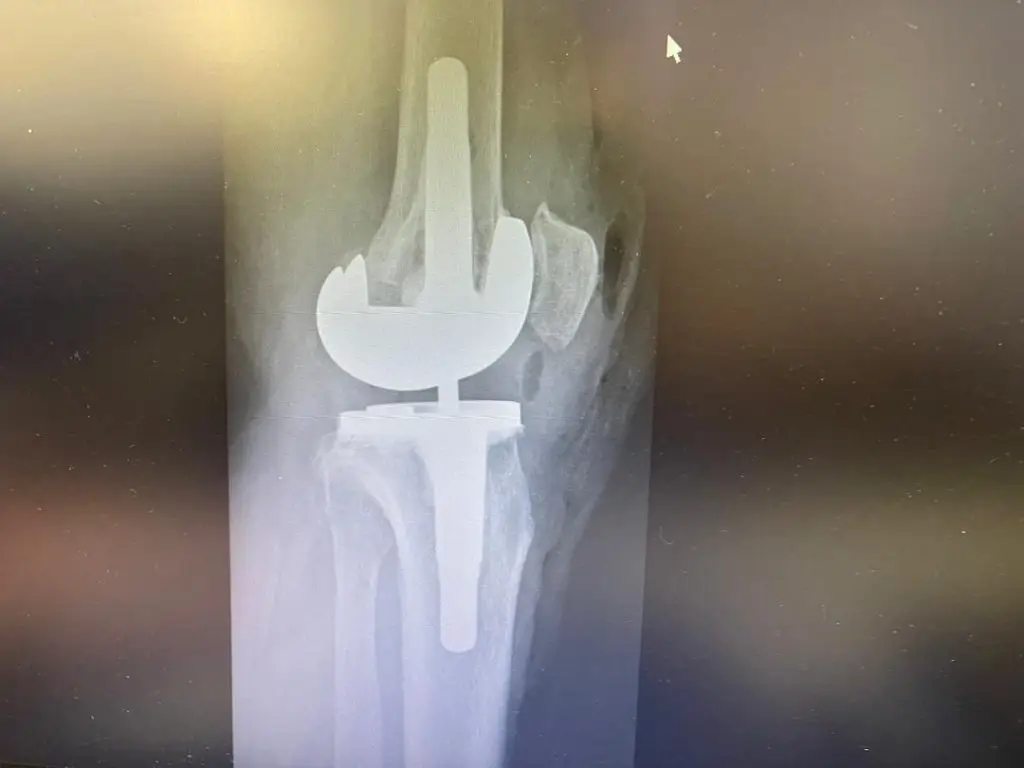

تعویض مفصل زانو یا Total Knee Replacement (TKR) که با نام آرتروپلاستی زانو نیز شناخته میشود، یکی از موفقترین جراحیهای ارتوپدی در سراسر دنیاست.

در این عمل، بخشهای آسیبدیده از مفصل زانو (غضروف و استخوانهای ساییدهشده) با قطعات مصنوعی از جنس فلز، سرامیک یا پلاستیکهای مخصوص جایگزین میشوند.

هدف این جراحی، کاهش درد، بهبود حرکت و بازگرداندن توانایی بیمار برای انجام فعالیتهای روزمره است.

- دوام بالا: مفاصل مصنوعی امروزی بین ۱۵ تا ۲۰ سال عمر مفید دارند و در بسیاری موارد بیشتر نیز دوام میآورند.